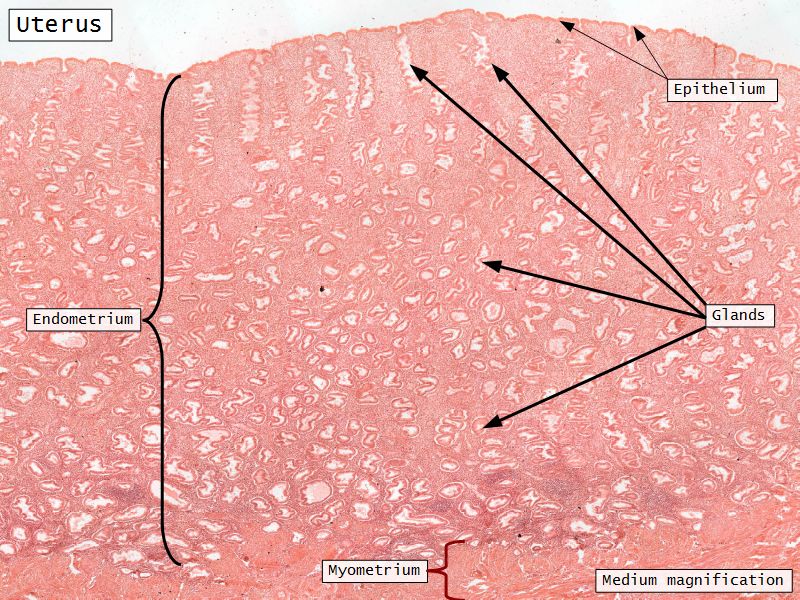

Endometrium

- Formation of placenta

- Hormonally modulated cyclic alterations

- menstrual cycle

- Two layers

- Thick superficial functional

- Deeper basal layer

- Separation indistinct

Endometrium

- Epithelium

- Simple columnar

- Two cell types

- Secretory

- Ciliated

- Glands

- Similar but fewer ciliated

Endometrium Stroma

- Mesenchymal-like CT

- Reticular fibres

- Stellate-shaped cells

- Macrophages

- Lymphoid elements

- Functional layer

- Basal layer

Endometrial glands

- Extend through basal layer

- Source of cells to reestablish endometrium

Blood supply

- Originate from myometrium

- Helical arteries

- Extend into functional layer

- Straight arteries

- Terminate basal layer

Myometrium